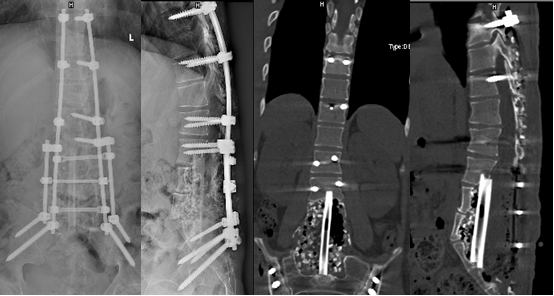

3月22日,经过前后总计约9个小时的手术后,患者顺利回到病房。在医护团队的精心照护下,患者术后一周佩戴腰部支具可下床活动,复查显示肿瘤无残留,内固定稳定在位,脊柱胸腰段后凸角为16°,基本与常人无异。4月4日,患者恢复良好,平安出院。

术后影像学检查